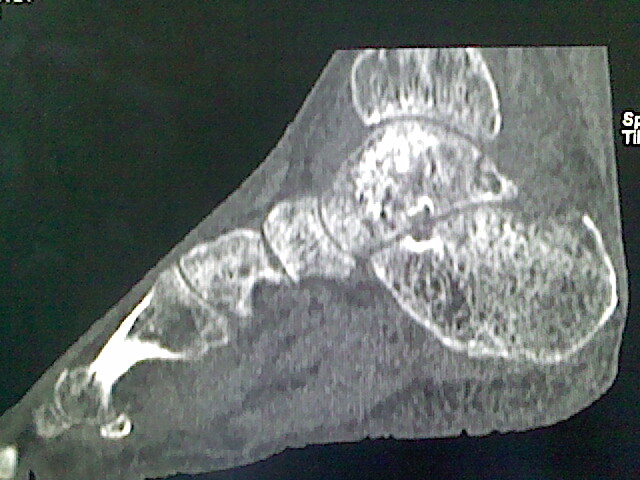

标题: CT16814:男,76岁,左小腿疼痛,不能站立 大家给看看 [打印本页]

男,76岁,左小腿疼痛,不能站立

本例骨质改变主要表现为滑膜或韧带区的骨侵蚀融解(胫腓联合区骨质破坏无硬化边),距骨后部骨质破坏区有硬化边及死骨样改变.所以,本例考虑关节结核可能性大,绒毛膜结节性滑膜炎多发于中年,且极少见于膝髋以外的关节,骨质硬坏也以压陷吸收为主,有明显的硬化边,骨膜增生呈结节状(可以mr鉴别),所以本例暂除外.

另不除外可引起相似表现的其他炎症如布氏杆菌性关节炎等